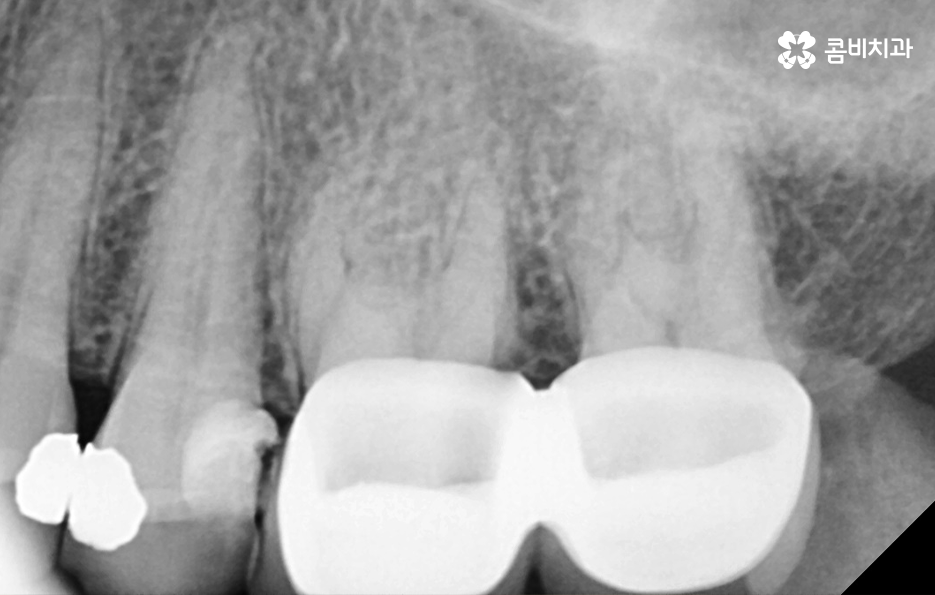

많은 환자분들께서 이미 충치 치료를 했던 부위인데 왜 또 충치가 생길 수 있는지 의아해 하시는 분들도 계실 거예요. 충치 치료를 했던 부위를 살펴보면 보철 재료와 치아 사이에 경계면이 있다는 것을 알 수 있는데요.

충치 치료 후에는 보철물과 치아 사이의 경계선 부분에서 보철물의 접착제가 녹는 경우도 있고 보철물 자체의 손상이 발생되는 경우도 있으며 보철물은 멀쩡하더라도 자연치아가 마모되고 깨지는 등의 문제가 발생될 수 있는데 이때 보철물과 치아 사이에 틈이 발생되면 치아 내부로 세균이 침투하여 2차충치가 발생되는 원리라고 할 수 있어요

이처럼 2차충치가 치아 내부로 진행된 경우에는 치아 구조의 특성상 치아의 겉면에 비해 내부가 좀더 약하기 때문에 충치는 비교적 쉽게 내부로 깊어질 우려가 있으며 신경조직에 손상이 발생한 경우에는 신경치료를 해야 하기 때문에 자연치아의 손상이 그만큼 커질 수 있어요

이러한 문제는 치아 내부에서 발생하기 때문에 눈으로 살펴볼 때는 상태 확인이 어렵고 명동치과 주기적으로 검진을 하지 않는다면 통증을 통해 뒤늦게 문제를 인지하기 때문에 치료 시점도 초기치료는 놓친 경우가 대부분이라 할 거예요